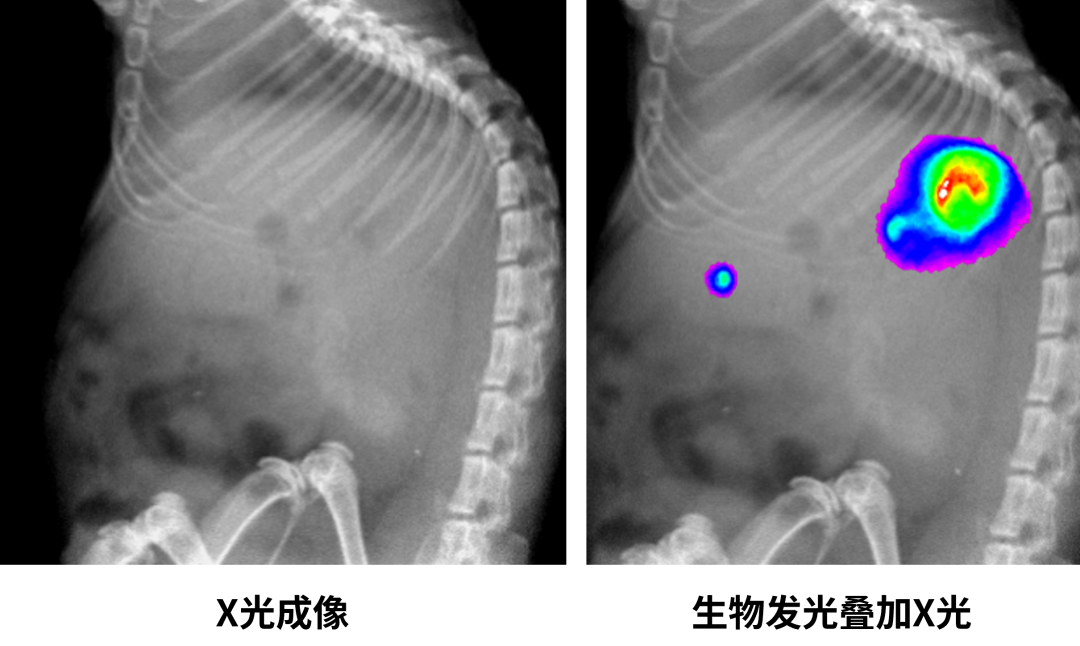

1. 生物发光成像(BLI)

利用生物发光活体成像技术观察肺癌肿瘤生长情况

模型构建:转染荧光素酶基因(如Luc2)至目标细胞

底物注射:腹腔注射D-荧光素钾盐(150 mg/kg)

信号采集:注射后10-15分钟,暗箱内用高灵敏度CCD相机捕获(曝光60-300 s)

数据分析:通过ROI定量光子通量(photons/s/cm²/sr)

3. X光成像

X-Ray成像

样本准备:麻醉固定,或注射碘海醇等造影剂

参数设置:电压40-60 kV,电流0.5-1 mA(小动物)

图像采集:曝光时间0.1-5 s,多角度拍摄(可选CT 3D重建)

三维重构:通过Micro-CT获取10-50 μm分辨率体数据

生物发光在乳腺癌研究中的应用